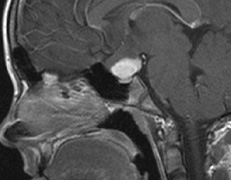

Optic nerve gliomas may involve the optic chiasm and be associated with endocrine disorders or nystagmus.68–70 Surgical excision of chiasmal gliomas (Fig. 6) carries a high risk of visual loss. Invasion of the hypothalamus or the third ventricle carries a poor prognosis, with greater than 50% 15-year mortality rate.71 One review of radiation treatment for chiasmal gliomas collated data from small case series and found no significant long-term improvement in visual function, progression, or mortality with radiation treatment.71 Other reports suggest that radiation doses over 4500cGy improve symptoms and slow progression of chiasmal gliomas over several years.72 Adequate tumor coverage by radiotherapy results in irradiation of normal brain and nearly all children need hormone replacement.73 Chemotherapy is an alternative.74,75

Fig. 6. Surveillance images of a 12-year-old girl with NF1 and an optic nerve glioma which has extended to involve the chiasm. Pre- (a) and postcontrast (b) T1-weighted coronal images reveal a large suprasellar mass with an enhancing component (arrow) seen separately from the normally enhancing pituitary gland. (c) Axial scans through the suprasellar cistern show the tumor is high signal on T2-weighted scans. (d) Enlargement of the chiasm, optic nerve and hypothalamus is visible on the post-contrast T1-weighted sagittal image. Although optic nerve glioma usually has a good prognosis (with visual function often remaining stable in the absence of any intervention66,67), chiasmal involvment is a poor prognostic indicator. A sign of chiasmal involvment may be new onset of endocrine disorders or nystagmus. Surgical excision of chiasmal gliomas carries a high risk of visual loss.68–70